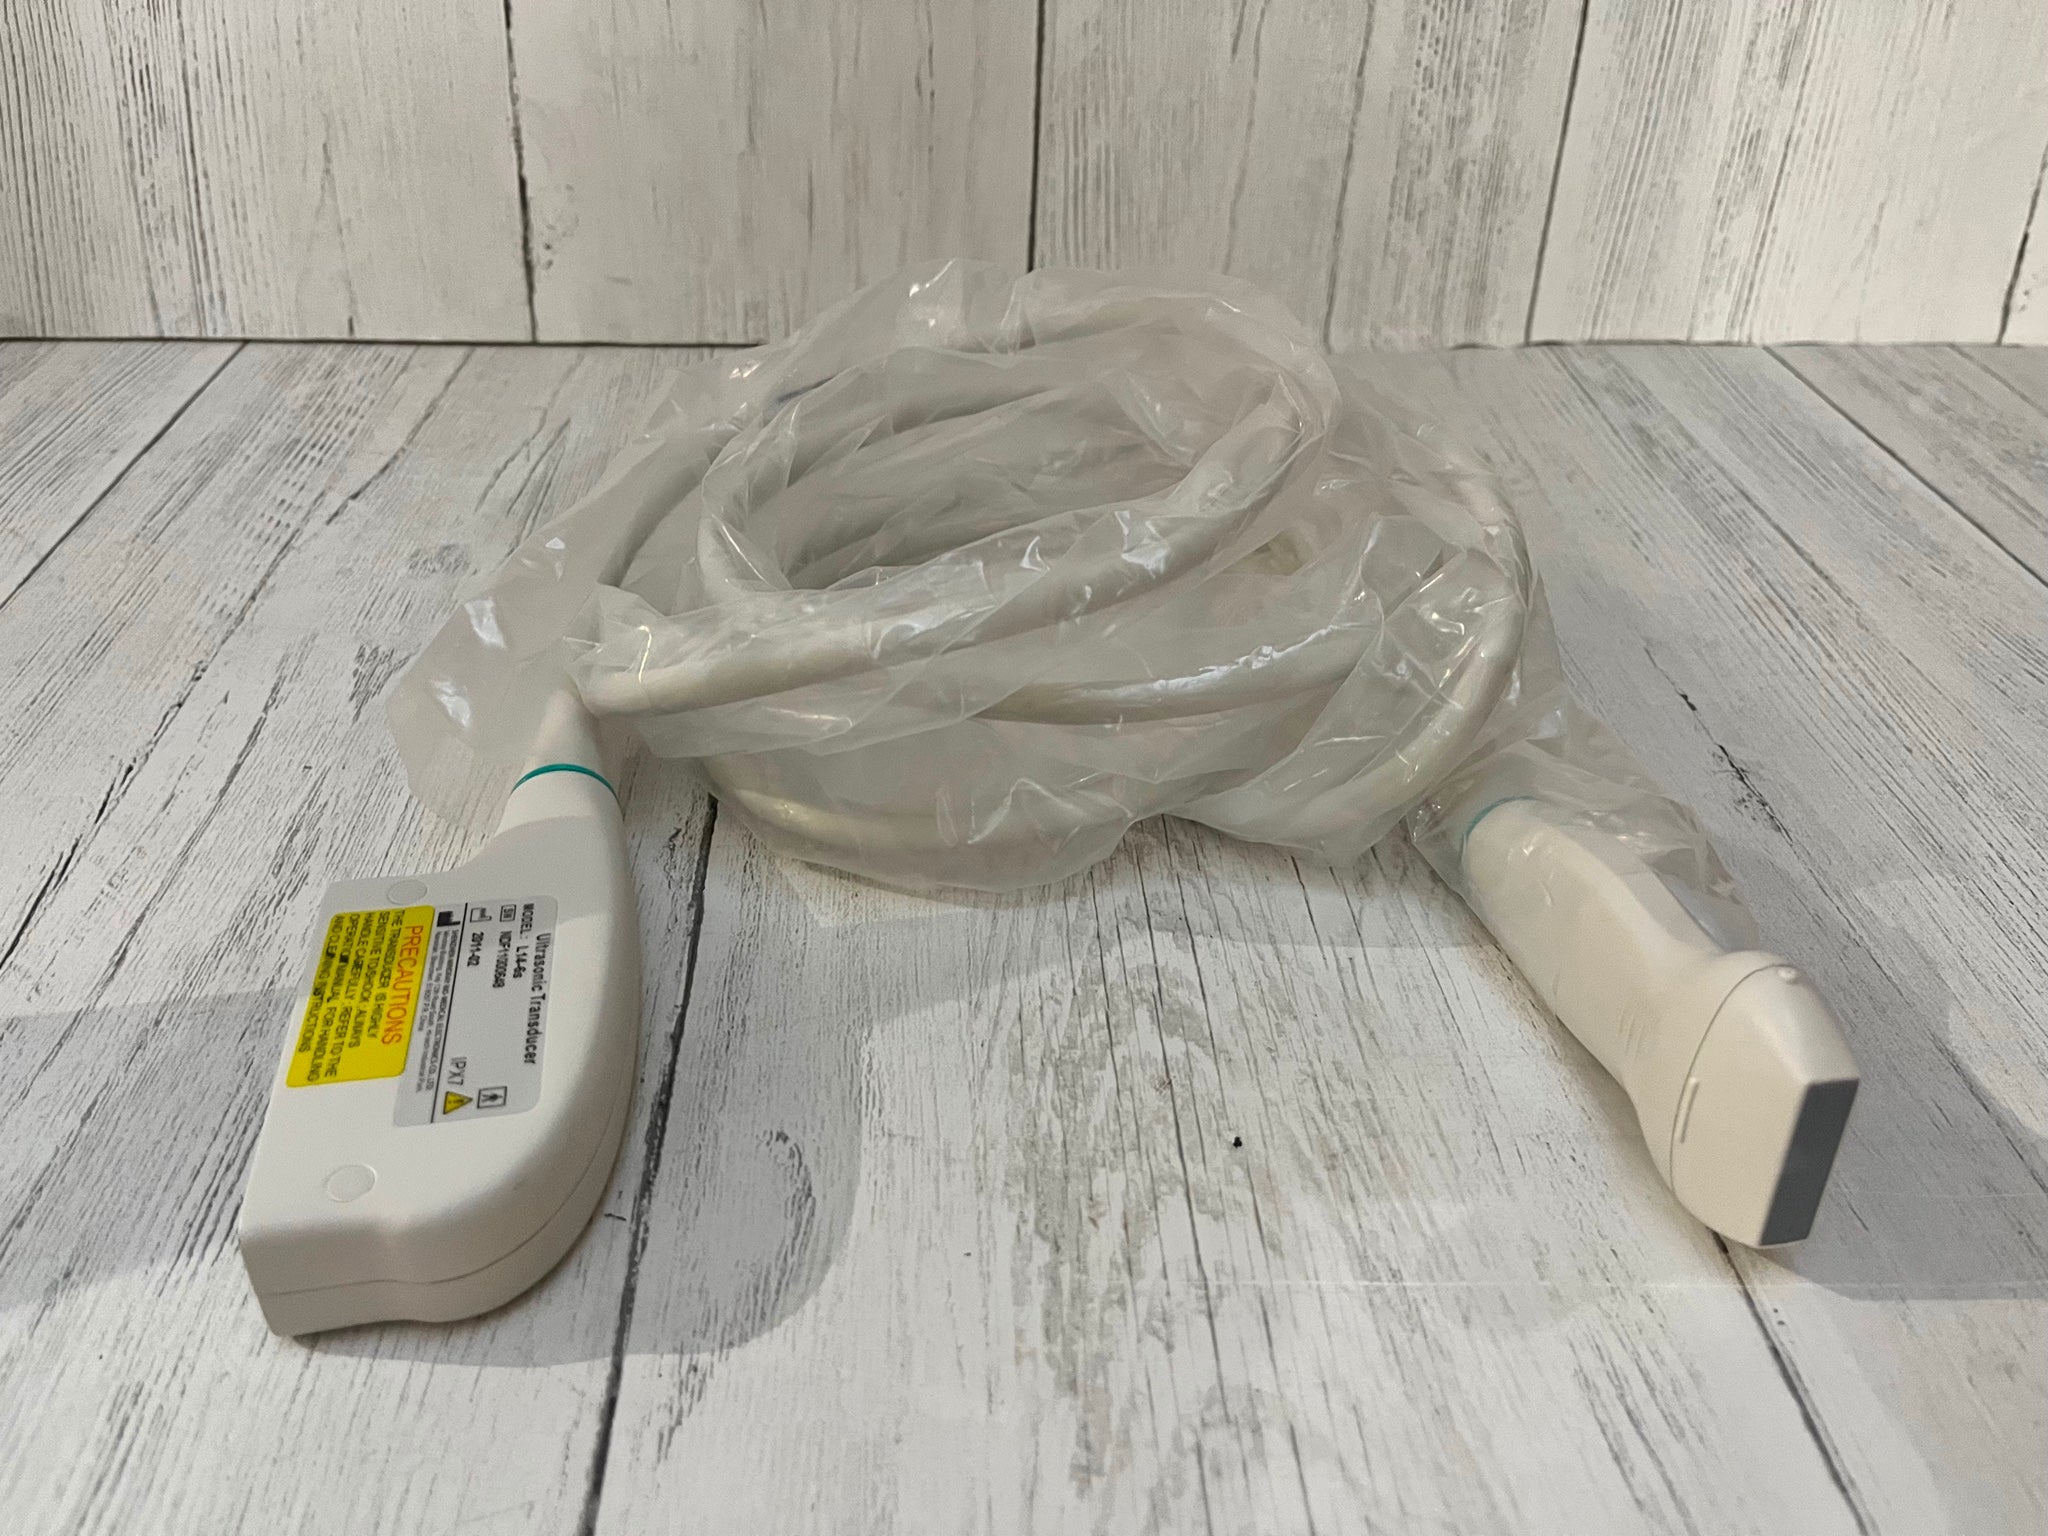

DIAGNOSTIC ULTRASOUND MACHINES FOR SALE

Ultrasound Scanner Machine 7.5Mhz Linear Probe Free 3D modul Vascular Scan Fast 190891351487

Sale price$ 1,507.97

Regular price$ 1,838.99